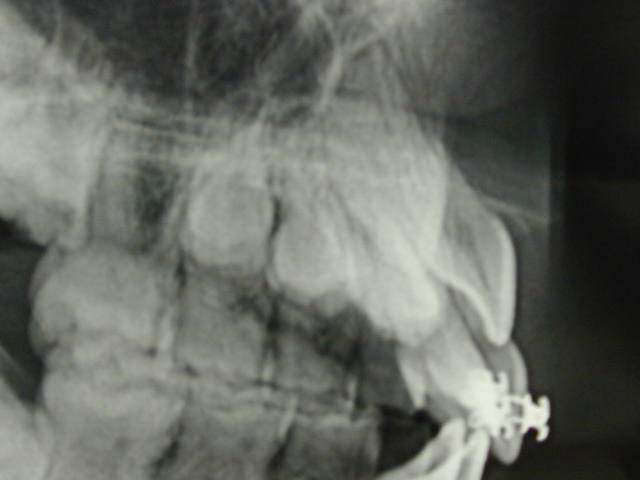

Patiente de 9ans, retard de l'évolution de la 11 par chute prématurée de la 51. J'ai prévu de mettre un sectionnel 21-12-22 et un UA afin de garder la position des incisives dans le sens antéro- postérieur.A quoi correspond cette image radio et que feriez- vous dans ce cas. Merci de m'éclairer.

"dens in dente" ??? pas d'autre explication à l'horizon?

Odontome qui serait dans le plan frontal de ta prise radiographique de 11 et qui bloque l'erruption.

Si tu peux , essaye des incidences plus obliques et meme une incidence verticale venant du bas pour voir si une "soudure "existe. En gros, savoir si on a une ou deux pièces dentaires.

Oui, dam-dam, tu as raison, il ya plus de chances en effet d'une dens in dente qu'un odontome qui est en général "entre" 2 dents.

En regardant bien la dent lactéale il semblerait qu'elle soit géminée??????

En lisant sur le net (google: orthodontics, "dens invaginatus"), il existe tres souvent des problemes de resorption radiculaire. En plus, j'ai lu qque cette dent a de fortes chances d'etyre "bosselée", c a dire pas belle.

Donc, chirurgie, risque de blocage, risque de resorbtion. Et tous ces obstacles passés, dent affreuse.

Lève quand meme a coup sur la probabilité d'odontome ou d'une dent surnuméraire, meme s'il y a peu de chances. Avoue qu'il est dur de porter un diagnostic infaillible.

dens in dente(odontome invaginé)

le pertuis palatin=la dent invaginée

dès que la dent sera sur l'arcade,obturer au composite ou autre mais étanche(!!!) le pertuis palatin qui est une porte d'entrée jusqu'à la pulpe

et le traitement canalaire d'une telle dent est quasi infaisable avec de bons résultats à long terme

compte tenu de l'age,faire de la place et tracter(avis odf)

surnuméraire en superposition?

il me semble voir comme adhoc,une racine separee et une petite couronne en arriere de la 11